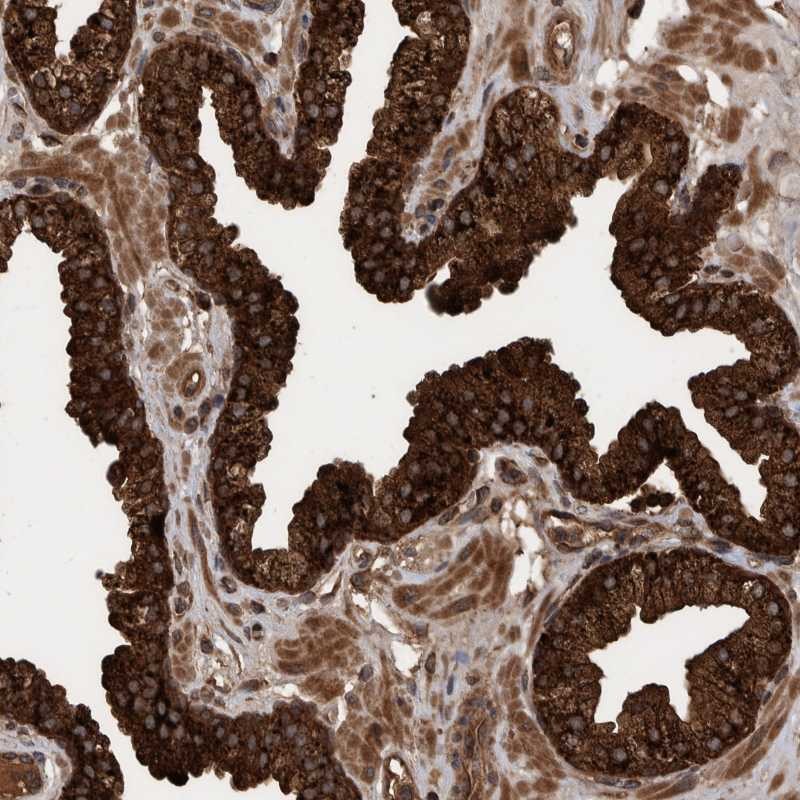

Immunohistochemical staining of human prostate shows strong cytoplasmic positivity in glandular cells.